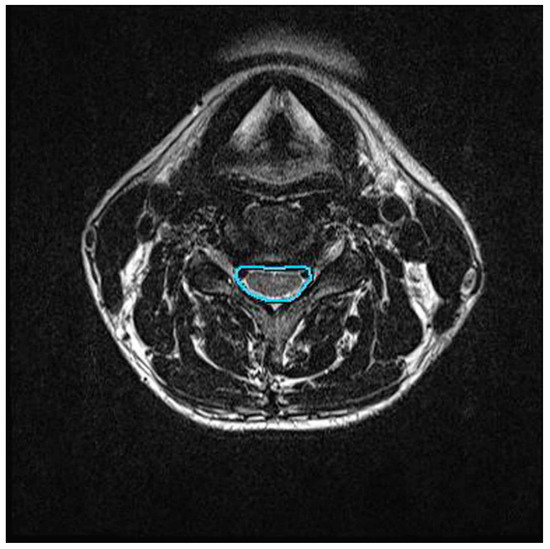

2.4.2. Central Canal Area Assessment

| Central canal area (mm2) | 130.9 ± 40.5 | 136.0 ± 43.2 | <0.001 * |

| Central canal area (mm2) | 137.9 ± 37.6 | 136.7 ± 41.4 | 0.549 |

| Central canal area (mm2) | 5.1 ± 5.3 | −2.5 ± 5.8 | 3.7 | <0.001 * |